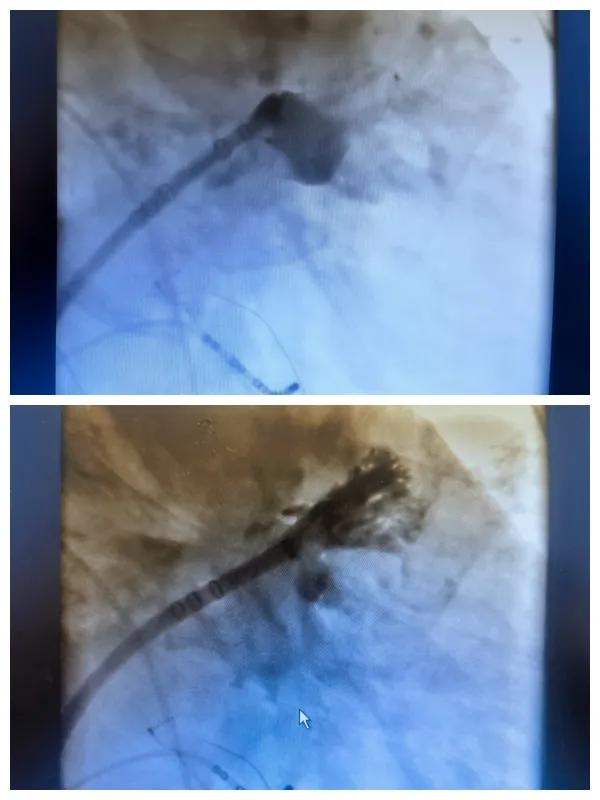

漯河市二院成功開(kāi)展房顫射頻消融術(shù)+左心耳封堵WM FLX一站式手術(shù),再攀“心”高峰!

房顫射頻消融術(shù)+左心耳封堵WM FLX一站式手術(shù)

6月26日,市二院成功為一名老年房顫患者實(shí)施了房顫射頻消融術(shù)+左心耳封堵WM FLX一站式介入治療,標(biāo)志著醫(yī)院在心律失常介入治療領(lǐng)域邁出了嶄新的一步,開(kāi)啟了新的治療篇章。

本次手術(shù)特邀我國(guó)著名心血管內(nèi)科專(zhuān)家、河南省胸科醫(yī)院黨委書(shū)記袁義強(qiáng)及血管內(nèi)科七病區(qū)主任黃瓊教授蒞臨指導(dǎo),市二院院長(zhǎng)王瑾帶領(lǐng)心血管內(nèi)科電生理等專(zhuān)家團(tuán)隊(duì)緊密合作,一次性解決了患者房顫、血栓兩大困擾,也使患者告別了終身服用抗凝藥的痛苦,極大地降低了患者的經(jīng)濟(jì)和用藥負(fù)擔(dān)。

為了讓患者得到全面、綜合的治療,經(jīng)過(guò)團(tuán)隊(duì)術(shù)前充分討論,并征得家屬同意,心血管內(nèi)科團(tuán)隊(duì)決定采用目前國(guó)內(nèi)外先進(jìn)的房顫射頻消融術(shù)+左心耳封堵WM FLX一站式介入微創(chuàng)手術(shù)來(lái)治療老人的疾病。整個(gè)手術(shù)過(guò)程圓滿(mǎn)順利,術(shù)后何大爺各項(xiàng)體征正常,蘇醒后順利返回病房。